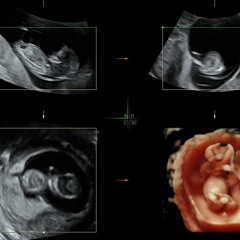

Womb 2139

-xXMing